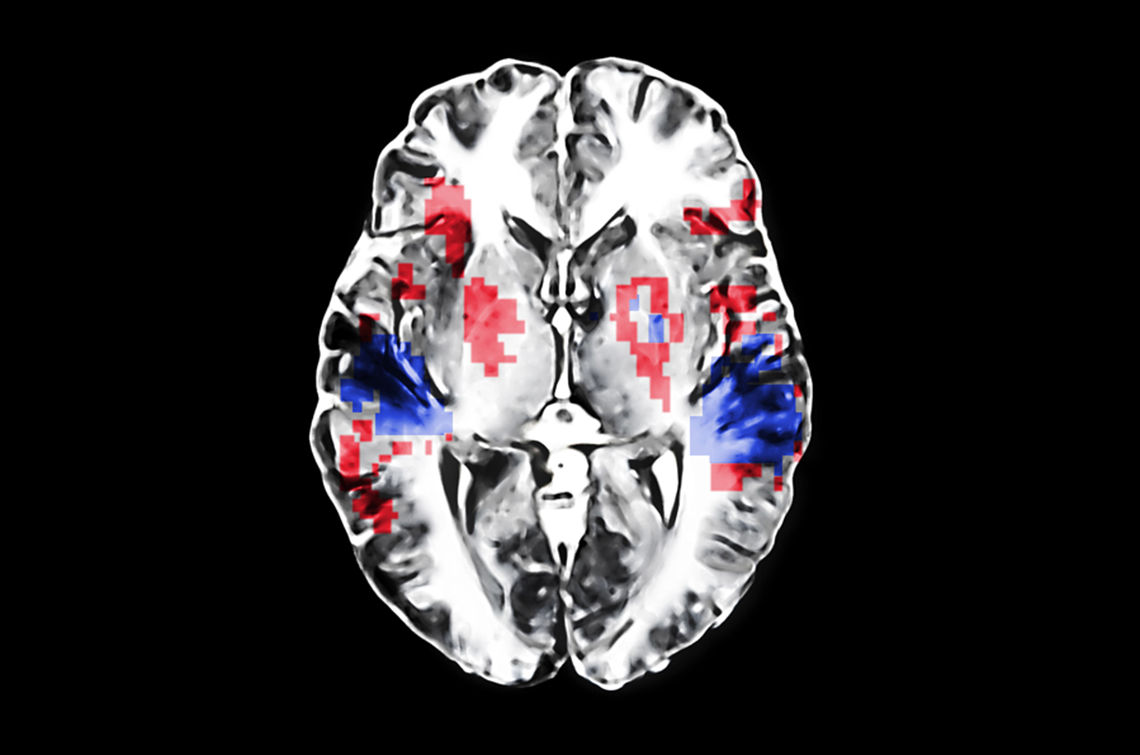

Several theories elucidate why music positively affects our cognitive functions. First and foremost, there’s the concept of neural entrainment, where rhythmic auditory stimuli synchronize with the brain’s natural oscillations, effectively enhancing the processing speed and efficiency of mental tasks. For example, listening to a steady beat while playing brain-training games could bolster memory retention, enabling players to recall strategies and patterns more effectively.

Delving into the neuroscience reveals how sound influences our memory pathways. Research has shown that engaging with familiar music activates specific neural pathways associated with memory retrieval, intertwining the auditory stimulus with cognitive recall. The connection formed can be so robust that, in experimental settings, subjects exposed to sound while learning new information demonstrated remarkable benefits in memory performance when tested later in similar auditory contexts.